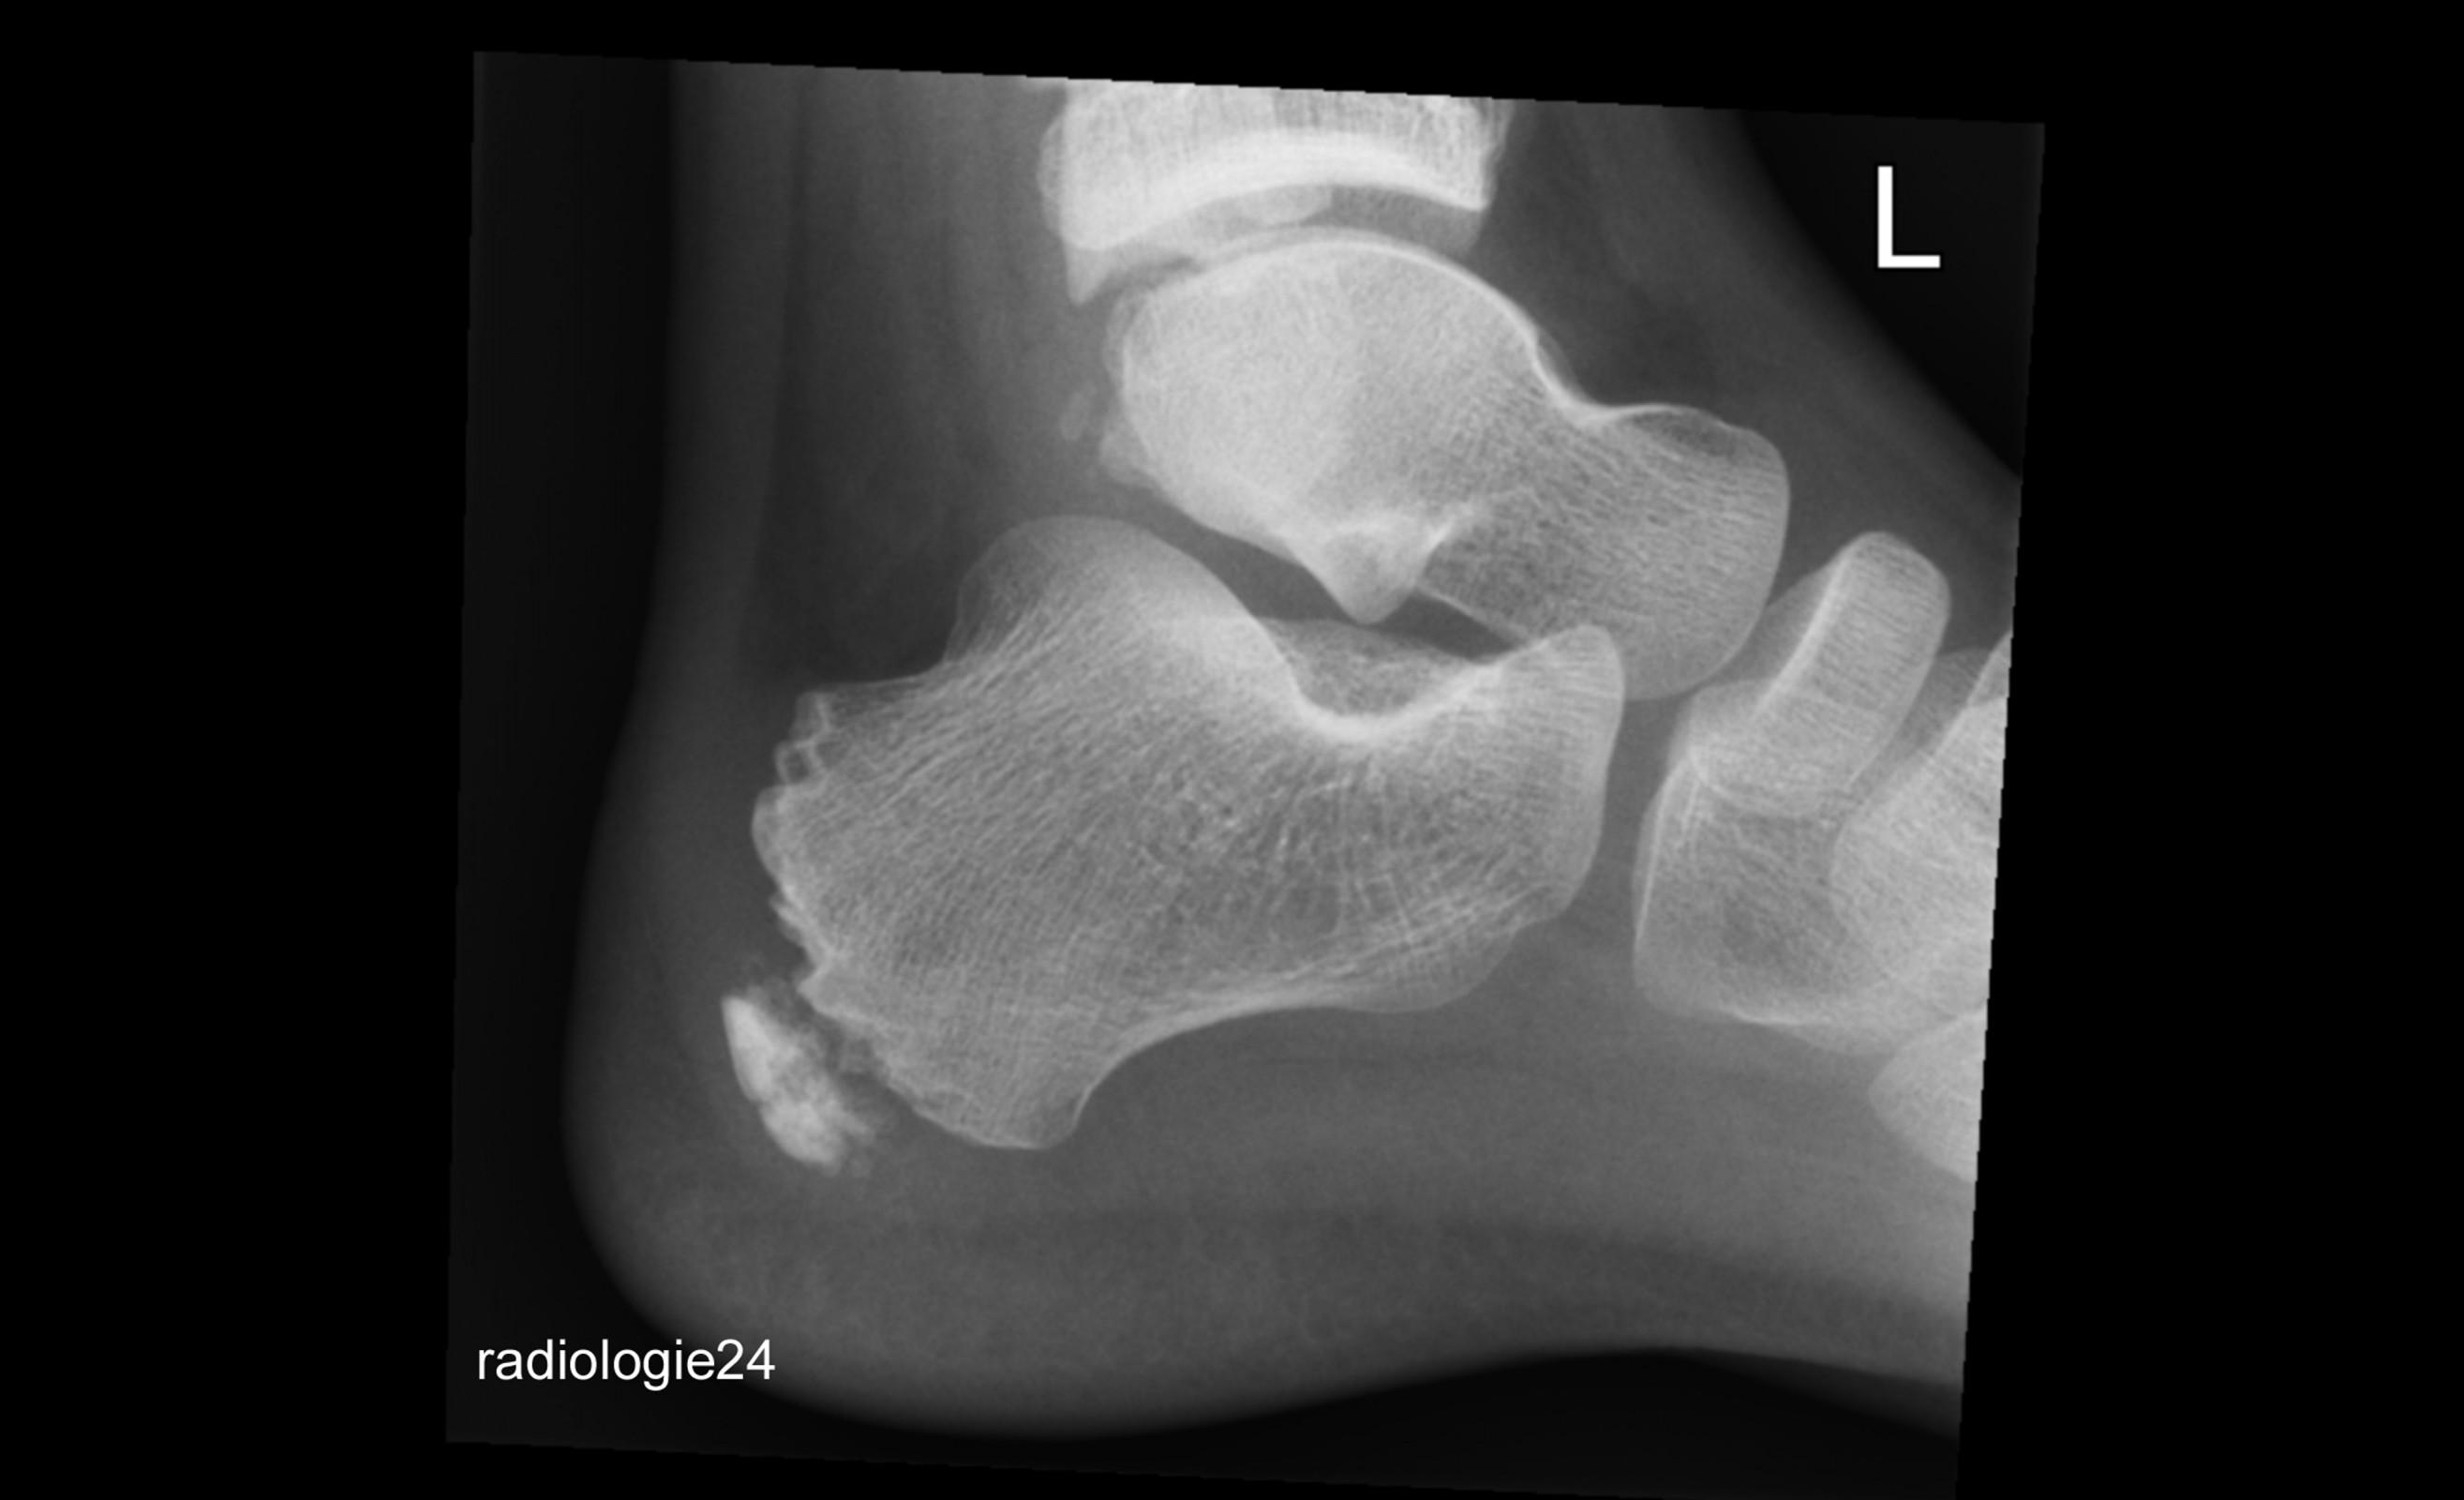

Röntgenfall des Monats April 2018 mit Auflösung

10 jähriger Patient Schmerzen im Bereich des Achillessehnenansatzes nach Fussballspiel. Ihre Diagnose? Weitere Abklärung?